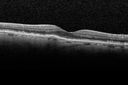

CNVM - new CNVM no leakage on OCT

amdcnvmnofluid_rosh09.jpg

10 files, last one added on Apr 14, 2011

Album viewed 1170 times